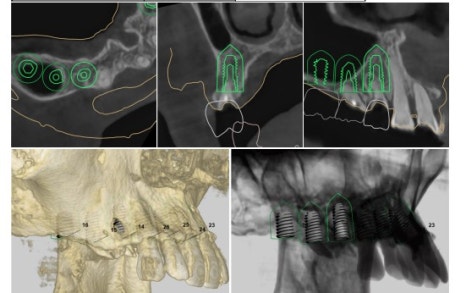

그로 인해 3D 임플란트 내비게이션이라는 장치가 있습니다.

이런 식으로

환자분의 데이터를 바탕으로 모의 수술을 하고

그로 인해 임플란트 수술 방향을 정한 상태로 수술을 들어갑니다.

뼈가 너무 얇지만 광범위한 뼈이식 동시에

임플란트까지 식립하는 것을 목표로 하고

수술시간 단축을 위해 3D 내비게이션 가이드를 제작했습니다.

환자분의 데이터를 통해

아래와 같은 3D 내비게이션 가이드를 제작합니다.

조심스럽고, 신중하고, 빠르게 수술을 진행했습니다.

상기 환자분 같은 케이스는

잇몸 절개 없이 수술은 불가능하기 때문에

3D 내비게이션 가이드의 장점을 100% 활용할 수 없지만

빠른 식립을 위해 사용하였습니다.

다행히 골이식과 동시에 임플란트를 수술 성공하였습니다.